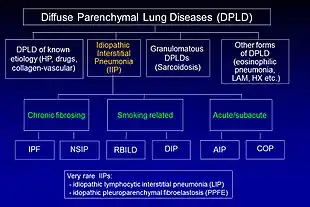

Idiopathic pulmonary fibrosis (IPF) belongs to a large group of more than 200 lung diseases known as interstitial lung diseases (ILDs), which are characterized by the involvement of the lung interstitium,[9] the tissue between the air sacs of the lung. IPF is one specific presentation of idiopathic interstitial pneumonia (IIP), which is in turn a type of ILD, also known as diffuse parenchymal lung disease (DPLD).

The 2002 American Thoracic Society/European Respiratory Society (ATS/ERS) classification of IIPs was updated in 2013.[9] In this new classification there are three main categories of idiopathic interstitial pneumonias (IIPs): major IIPs, rare IIPs, and unclassifiable IIPs. The major IIPs are grouped into chronic fibrosing IPs (this includes IPF and non-specific interstitial pneumonia [NSIP]); smoking-related IPs (i.e. respiratory bronchiolitis–interstitial lung disease [RB-ILD] and desquamative interstitial pneumonia [DIP]); and acute/subacute IPs (i.e. cryptogenic organizing pneumonia [COP] and acute interstitial pneumonia [AIP]).[9]

The diagnosis of IIPs requires exclusion of known causes of ILD. Examples of ILD of known cause include hypersensitivity pneumonitis, pulmonary Langerhan's cell histiocytosis, asbestosis, and collagen vascular disease. However, these disorders frequently affect not only the interstitium, but also the airspaces, peripheral airways, and blood vessels.[9]